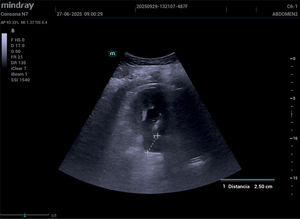

Cuando el cólico renal sigue doliendo, ¿entonces qué?